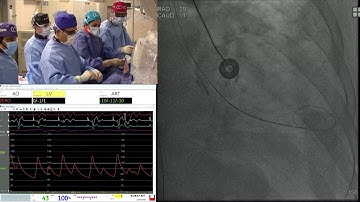

Live Case 1 and 2 Evolut R ViV SAPIEN 3 ViV TAVR Sentinel Device